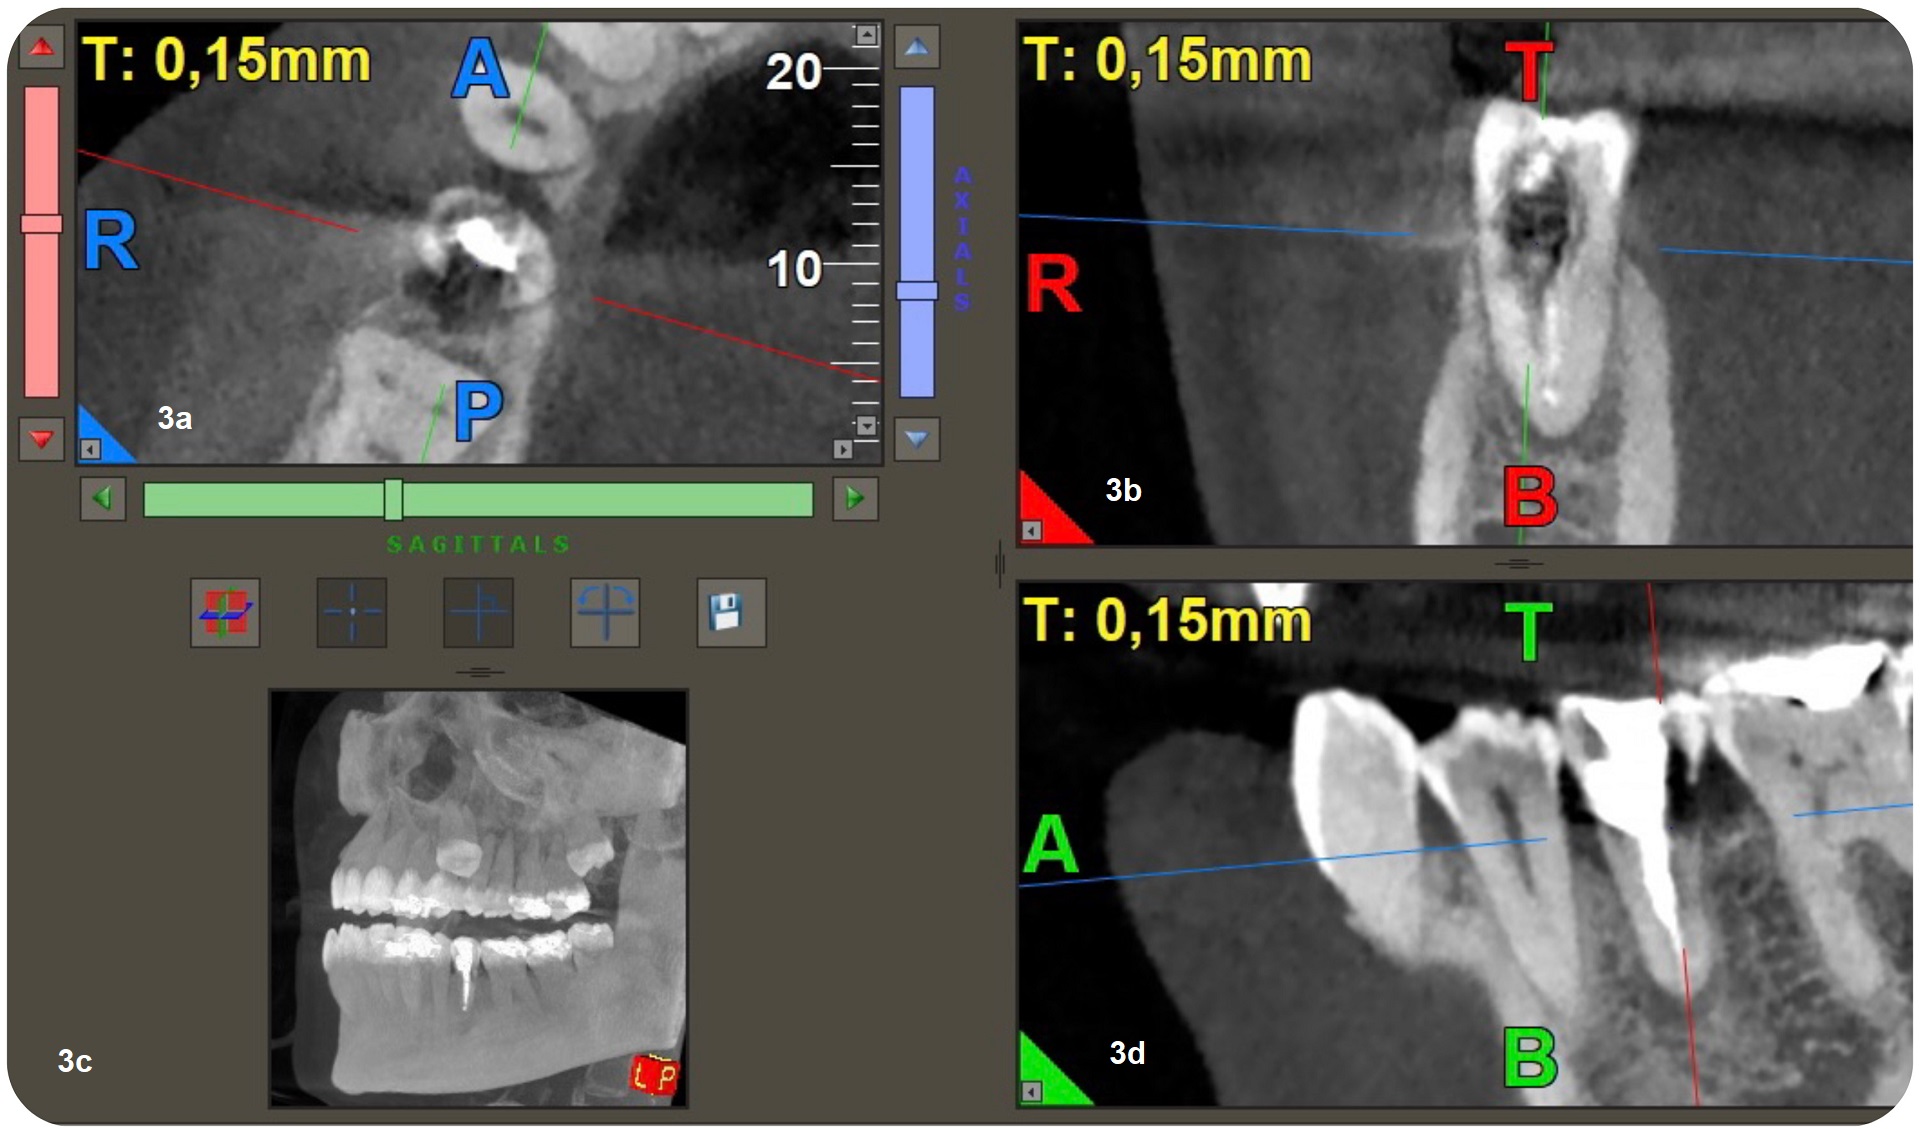

Figs. 3a–d: 3D reconstruction of axial section showing extension in mesial-distal direction (a). 3D reconstruction of a sagittal section showing the lesion extension, buccal-palatal direction (b). Coronal section of CBCT showing the extension of the periapical lesion and the resorptive defect (c). CBCT scan (d).

CBCT is a useful tool in endodontics, being used to assess the extent of an external cervical resorption defect, to detect and classify periapical periodontitis and to assess anatomical references with greater accuracy. Various studies have proved that CBCT is very helpful in diagnosis of this type of resorption.2–4 In the clinical case presented, an apical lesion and ECIR were observed, and CBCT was used to observe the size of the periapical lesion and the size and location of the resorption defect at the three spatial levels.